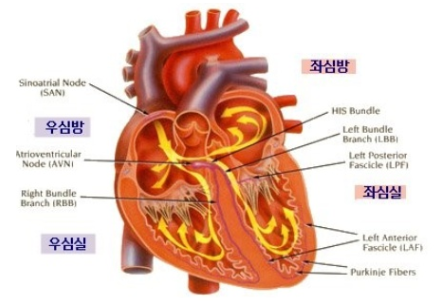

심장의 구조와 기능:

심근경색에 대해 알아보기 전에

심장이 어떻게 구성되어 있고

어떤 역할을 하는지

명확하게 이해하는 것이 중요합니다.

중요한 기관인 심장은 전신에

산소가 풍부한 혈액을 공급하는

중요한 역할을 합니다.

그것은 효과적인 혈액 순환을

보장하기 위해 함께 작동하는

4개의 챔버, 즉 2개 심방과

2개 심실로 구성됩니다.

1.1 심장: 구조 및 기능:

심장마비에 대해 자세히

알아보기 전에 심장이 어떻게

구성되어 있고 어떤 역할을 하는지

이해하는 것이 중요합니다.

심장은 몸 전체에 산소가

풍부한 혈액을 공급하는

중요한 기관입니다.

이것은 효율적인 순환을 보장하기 위해 함께

작동하는 4개의 챔버(2개 심방 및 2개 심실)로 구성됩니다.